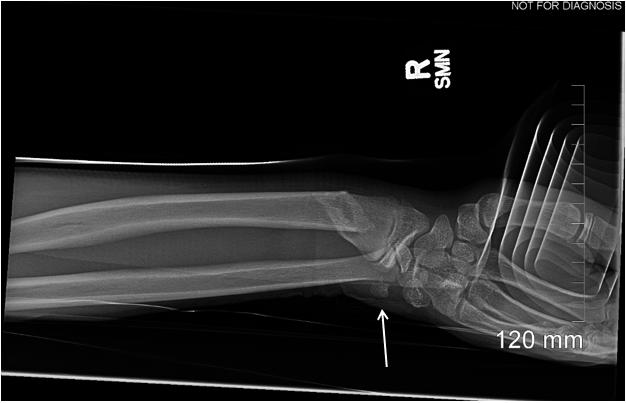

- CAL/AAEM News Service email updates - Discounted AAEM pre-conference fees

- And more!

CAL/AAEM NEWS SERVICE

- Healthcare industry news

- Public policy - Government issues - Legal cases and court decisions